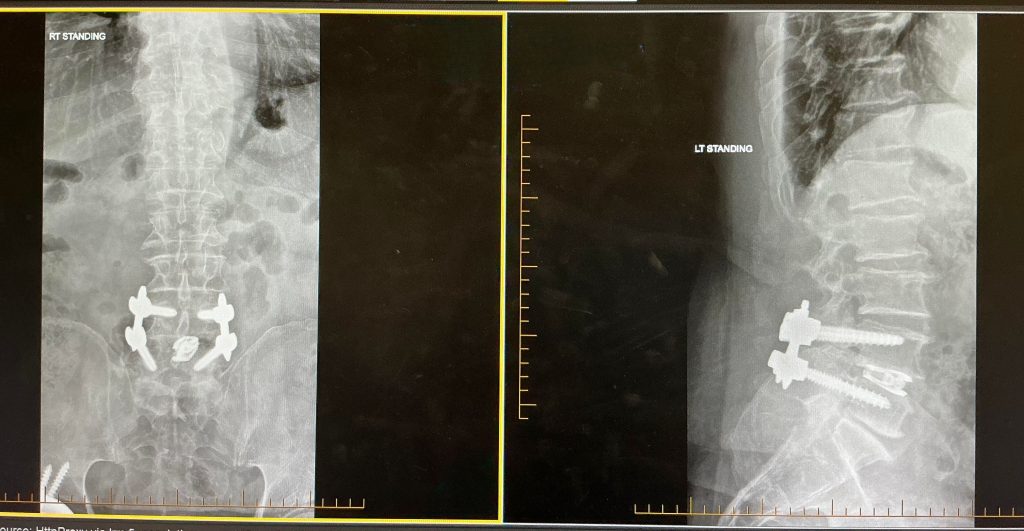

My Back Surgery in February of 2026 and my Rehab and Training

In my case, I had no option in the matter, in February of this year, I had my L-4 and L-5 disc fused and two rods installed, as indicated in the X-Ray above, to alleviate nerve pressure that I was experiencing. I can attest to the degree of the nerve issues, as many of you known all too well, isn’t fun. When the surgeon tells you that you can’t lift anything over 10 pounds or bend over pass your knee cap for the next 10- weeks, you have no choice but to STOP strength training and be patient during rehab. Now I know why they refer to us as patience; you got to have patience.